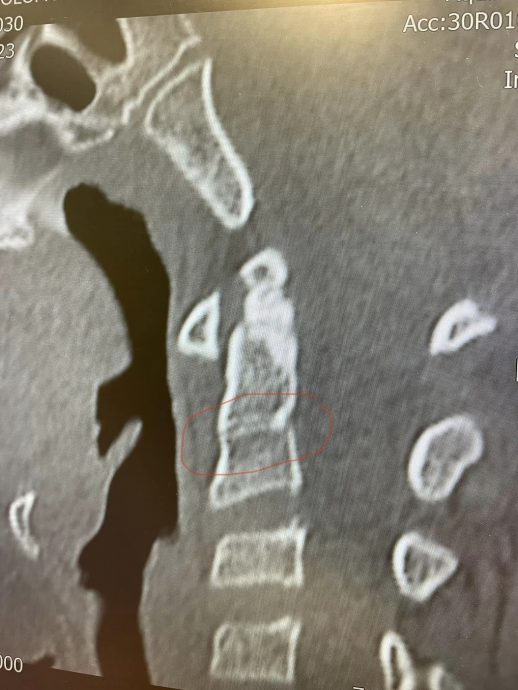

这名家长昨日在脸书贴文指出,事情发生在本周三上午体育课期间,有同学故意把球踢向她儿子,射中其颈项,扫描后发现脊椎骨有骨折痕迹,颈项肌肉胫骨严重受伤无法移动,肩膀高低不平,需要长久的物理治疗才可能痊愈。